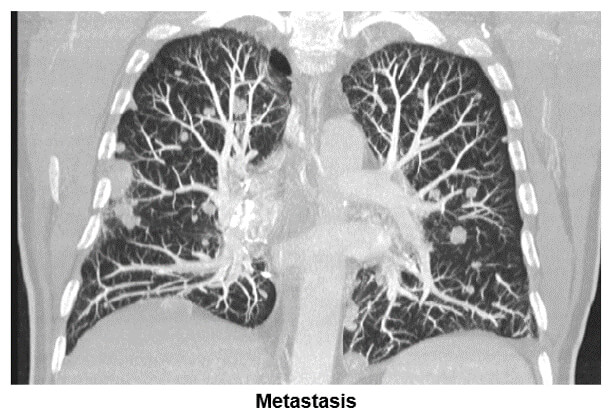

Nodules

The image shows where the maximum intensity projection is used to search for parenchyma solid nodule lesions. Notice the many metastatic lesions shown in both lung fields.